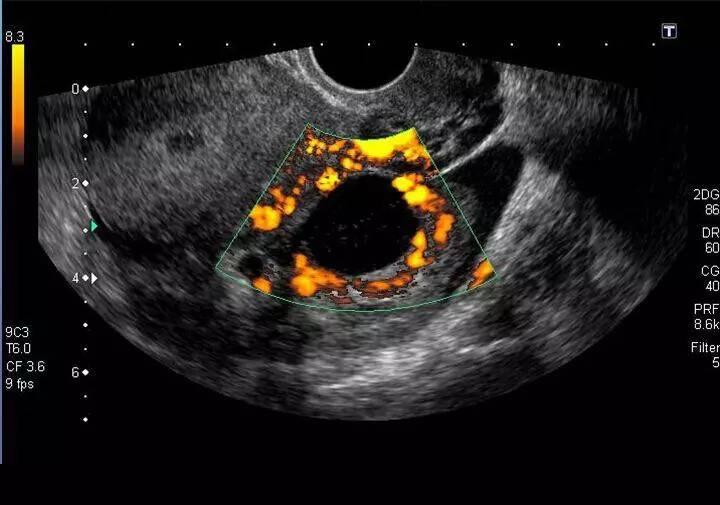

其次,就是B超检查了。

B超检查可以发现卵巢大小、形态是否正常,以及是否有卵巢囊肿的存在,可以帮助判别卵巢囊肿、卵巢畸胎瘤、卵巢恶性肿瘤等良性、恶性肿瘤。